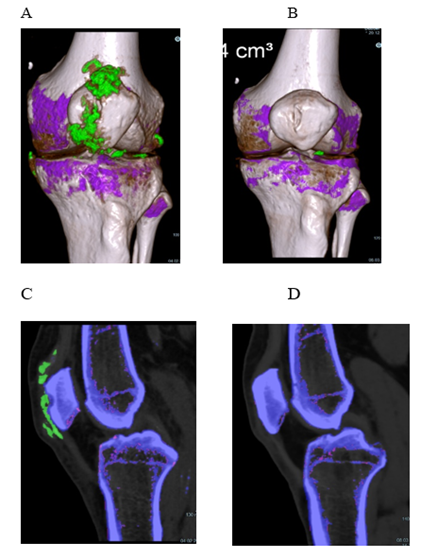

Patient 2 (Figure 2), 72 years, had had gouty attacks from the age of 60. He had started taking allopurinol, 300 mg/d, followed by an acute oligo-articular attack lasting three weeks by the time of his first visit. Treatment was switched to febuxostat, 80 mg/d, and increased to 120 mg/d 6 weeks later. His attack had subsided after a total of 6 weeks (3 weeks after switching to febuxostat). Another oligo-articular, migratory attack of 5 weeks duration started 8 weeks later. On a visual analogue scale, he rated his pain from 3 to 7, and he took ibuprofen as needed with a maximum of 3x 600 mg/d. Despite the presence of large crystal volumes (Figure 3; first DECT done 4 weeks after start of ULT; last attack ending 12 weeks after first DECT), no further acute attacks occurred. Throughout the course of combined treatment, the sUA levels fluctuated (Figure 2). Obviously, the patient was willing to co-operate, but frequently forgot to take single tablets, or took two when supposed to take one only, or did not ask for prescriptions in time. Nonetheless, his sUA remained in the low-normal to hypouricemic range and treatment success was as expected during an intensive course. A follow-up DECT taken 54 weeks after the first showed a single small deposit remaining in the lateral compartment of his left knee, not detectable by additonal imaging 2 years after start of treatment. After 3 years, the patient continued on allopurinol, 300 mg/d (sUA, 3.6 mg/dl).

Figure 3: Patient 2, dual energy computed tomography of his left knee. 3D reconstruction (A+B) and sagittal reformatted source images (C+D). – A, C and B, D: 4 weeks and 61 weeks, respectively, after start of uric acid lowering treatment